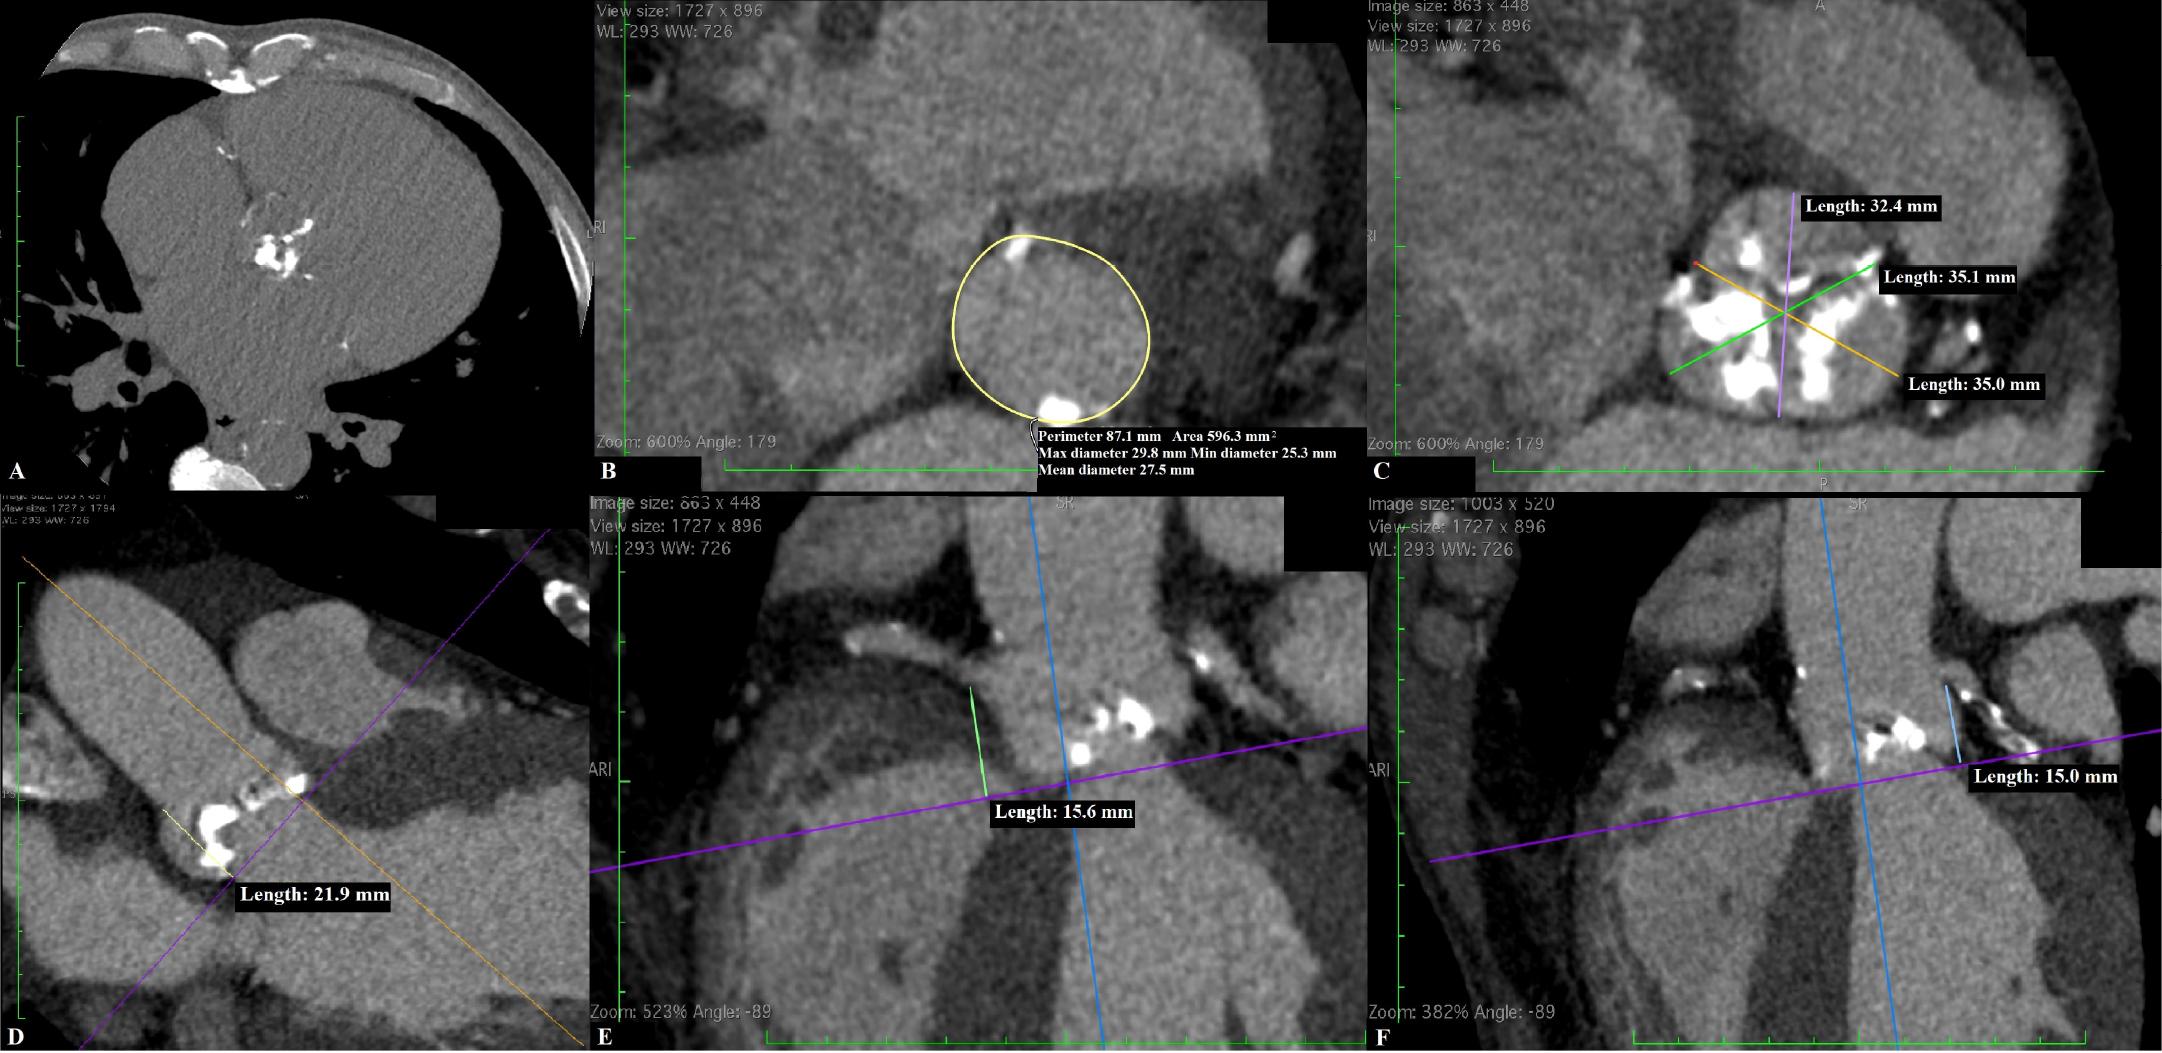

Computed tomography (CT) aortic root examination in a patient with aortic stenosis (AS) before transcatheter aortic valve implantation (TAVI). (A) Non-contrast CT showing intensely calcified aortic valve (calcium score 5888 AU); Contrast CT multiplanar reformatted images (during systolic phase 33 %) showing measurements of (B) the aortic annulus perimeter (87.1 mm) and diameters (maximum/minimum/mean 29.8/25.3/27.5 mm), (C) the sinuses of Valsalva diameters (32.4/35.1/35.0 mm), (D) the sinotubular junction height (21.9 mm), (E) the right coronary height (15.6 mm), and (F) the left coronary height (15.0 mm).